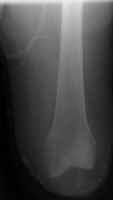

The knee disarticulation

results in an excellent weight-bearing stump. It is most often used in children and

young adults, but is nearly always avoided in the elderly and patient with ischemic

disease. Several advantages of the knee disarticulation include: 1) a

large end surface covered by skin and soft tissues that is naturally suited for weight

bearing; 2) a long lever arm controlled by strong muscles; 3)

increased stability of the patients prosthesis. A main disadvantage of the knee

disarticulation is cosmetic. The patient's prosthetic leg will have a knee that

extends far beyond his own knee in the sitting position. This tends to leave the

portion of the prosthesis below the knee dangling off the floor when the patient sits.

The image shown demonstrates an immediate post-operative knee disarticulation.